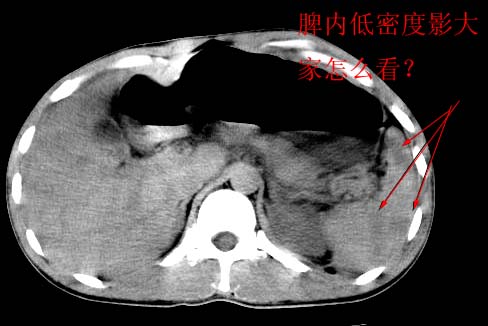

脾脏是问题还是伪影?

左肾挫裂伤并左肾薄膜下血肿;

左脾挫裂伤;